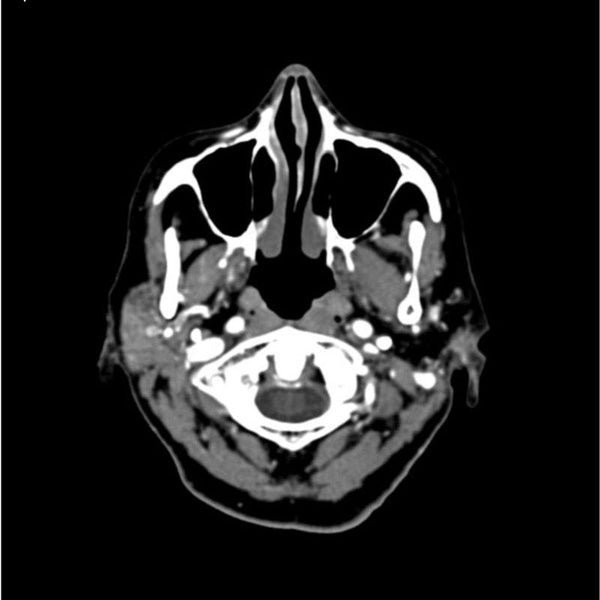

【コンビニ受取対応商品】 Head CTA and Training X-Ray and Scan CT for Phantom Neck ジャケット・アウターの詳細情報

CTA Head and Neck Phantom for CT Scan and X-Ray Training。CT203924 富士フイルム互換リサイクルトナーを安く注文 Ecoink.in。タイトスカート/SUPER100'sウール/オーバーペーングレン。ENVYMのコートです。数回着用しました。発送の都合で圧縮かけさせていただきます。。Detectors.png。新品 ユニバーサルオーバーオール ショートカバーオール レディース。極美品 RIVE DROITE ツイードジャケット